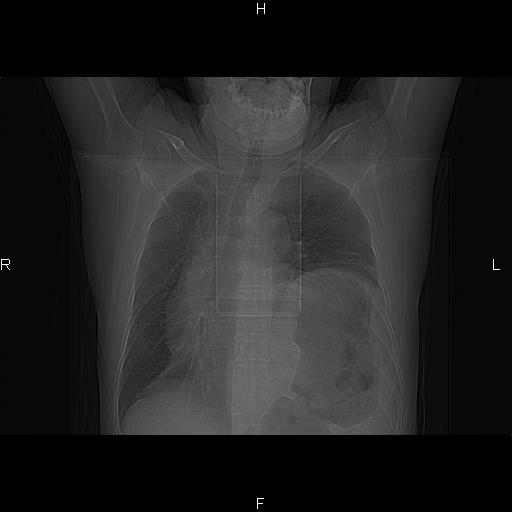

患者,男。50岁。近几日有咳嗽症状,无其他不适,既往病史无,考虑膈疝。请前辈们看看指导指导。

膈膨升,左下肺通气不良,膈肌好像还完整。

考虑左侧膈疝。

左侧膈疝。

符合隔膨升,膈肌较完整。